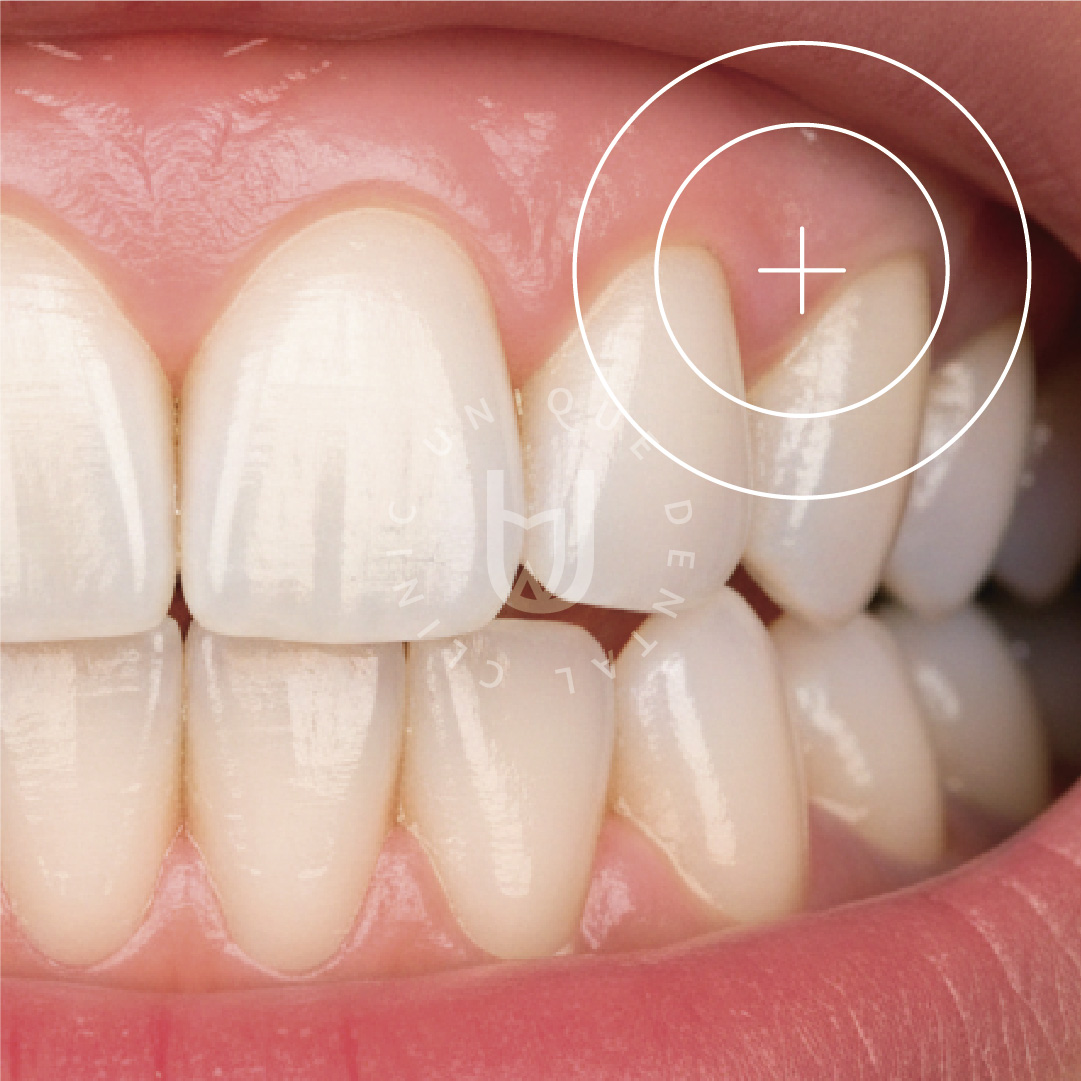

- Exposed tooth roots and increased sensitivity

- Gum tissue loss affecting smile aesthetics

Gum grafting is a periodontal procedure designed to restore lost or receded gum tissue. By reinforcing the gum line, this treatment protects tooth roots and creates a healthier environment for natural teeth and restorations.

- Customized gum graft techniques based on tissue condition and esthetic goals

- Healthier gum contours and enhanced smile aesthetics